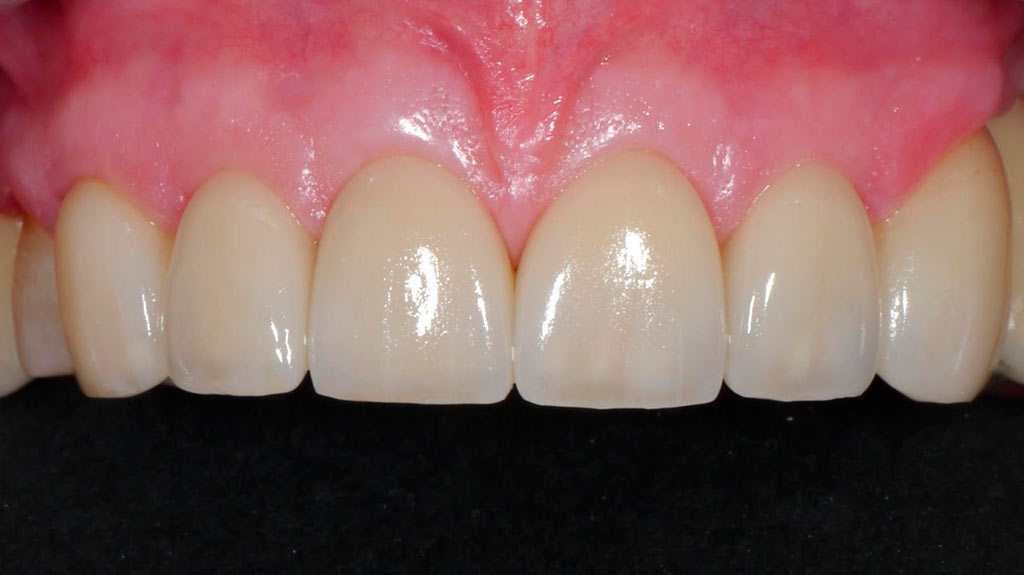

Completa inmediata,cirugía guiada, prótesis, puente de zirconio

Rehabilitacion de paciente con destrucción dental